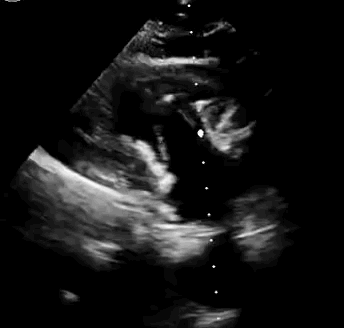

2021年11月14日星期日,復(fù)旦大學(xué)附屬中山醫(yī)院(以下簡稱中山醫(yī)院)葛均波院士團(tuán)隊(duì)成功應(yīng)用經(jīng)血管介入三尖瓣置換產(chǎn)品Lux-Valve Plus完成臨床前研究,并獲得圓滿成功!此次研究的成功預(yù)示經(jīng)血管三尖瓣產(chǎn)品Lux-Valve Plus已完成臨床前準(zhǔn)備,即將開啟后期的正式臨床研究!

上海中山醫(yī)院葛均波院士、錢菊英院長、周達(dá)新教授、潘文志教授、潘翠珍教授、李偉教授共同完成此次臨床前研究。術(shù)后葛均波院士對Lux-Valve Plus的器械操作性能給予了高度評價,DSA和超聲影像也顯示出在本次研究中Lux-Valve Plus的安全性和有效性俱佳。

本次臨床前研究經(jīng)右側(cè)頸靜脈置入LuX-Valve Plus輸送系統(tǒng)可調(diào)彎鞘管,在DSA及超聲引導(dǎo)下將人工三尖瓣瓣膜植入到原有三尖瓣位置,利用獨(dú)特的錨定技術(shù)將人工瓣膜支架可靠固定在預(yù)定的位置。

Lux-Valve是全球第一款具有我國完全自主知識產(chǎn)權(quán)的經(jīng)導(dǎo)管介入三尖瓣置換系統(tǒng),利用前瓣夾持及室間隔錨定的復(fù)合方式進(jìn)行瓣膜裝置的固定,不依賴瓣環(huán)徑向支撐力,同時采用自適應(yīng)復(fù)合裙邊材料,有效的貼合密封柔軟的三尖瓣瓣環(huán),針對于三尖瓣返流的患者有優(yōu)異的療效。Lux-Valve Plus采用全新的經(jīng)血管輸送系統(tǒng),經(jīng)頸靜脈入路創(chuàng)傷更小,可以進(jìn)一步降低手術(shù)風(fēng)險。相信在后期正式臨床研究開展中,Lux-Valve Plus必定會為更多的三尖瓣反流患者帶來福音。